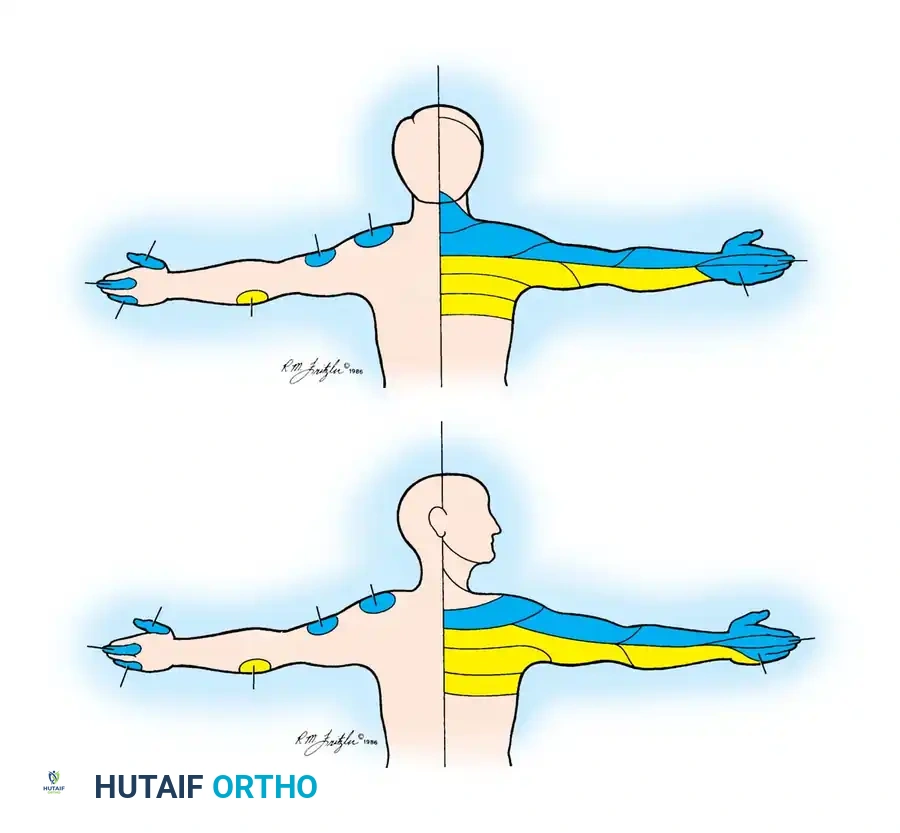

Neurological Level Localization

- C5 Nerve Root Compression (C4-C5 Disc):

- Sensory Deficit: Upper lateral arm and elbow.

- Motor Weakness: Deltoid (almost entirely C5) and Biceps (variable, dual C5/C6).

- Reflex Change: Biceps reflex (variable).

- C6 Nerve Root Compression (C5-C6 Disc):

- Sensory Deficit: Lateral forearm, thumb, and index finger.

- Motor Weakness: Biceps, Extensor Carpi Radialis Longus and Brevis.

- Reflex Change: Biceps and Brachioradialis reflexes diminished.

- C7 Nerve Root Compression (C6-C7 Disc):

- Sensory Deficit: Middle finger (variable due to dermatomal overlap).

- Motor Weakness: Triceps, Wrist flexors (Flexor Carpi Radialis), Finger extensors (Extensor Digitorum Communis).

- Reflex Change: Triceps reflex diminished.

- C8 Nerve Root Compression (C7-T1 Disc):

- Sensory Deficit: Ring finger, little finger, and ulnar border of the palm.

- Motor Weakness: Interossei, Finger flexors (variable), Flexor Carpi Ulnaris.

- Reflex Change: None.

- T1 Nerve Root Compression (T1-T2 Disc):

- Sensory Deficit: Medial aspect of the elbow.

- Motor Weakness: Interossei.

- Reflex Change: None.

In the classic clinical series by Odom, Finney, and Woodhall, considerable variability was noted. A diminished triceps reflex was the predominant reflex change in both C6 (56%) and C7 (64%) root compressions. Similarly, the index finger was the most common digit exhibiting hypalgesia in both C6 (68%) and C7 (70%) lesions.